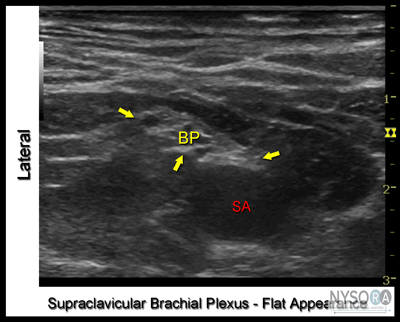

Figure 1: Supraclavicular brachial plexus; transducer position and needle insertion. Essentials ![]() Figure 2: Anatomy of the supraclavicular brachial plexus with transducer placement slightly obliquely above the clavicle (Cl). SA, subclavian artery; arrow, brachial plexus (BP). General Considerations The proximity of the brachial plexus at this location to the chest cavity and pleura, has been of concern to many practitioners (Figure 2). However, ultrasound guidance has resulted in a resurgence of interest in the supraclavicular approach to the brachial plexus. The ability to image the plexus, rib, pleura, and subclavian artery with ultrasound guidance has increased safety due to better monitoring of anatomy and needle placement. Because the trunks and divisions of the brachial plexus are relatively close as they travel over the first rib, the onset and quality of anesthesia is fast and complete. For these reasons, the supraclavicular block has become a popular technique for surgery below the shoulder. Ultrasound Anatomy The subclavian artery crosses over the first rib between the insertions of the anterior and middle scalene muscles, at approximately the midpoint of the clavicle. The pulsating subclavian artery is readily apparent, whereas the parietal pleura and the first rib can be seen as a linear hyperechoic structure immediately lateral and deep to it, respectively (Figure 3). The rib, as an osseous structure, casts an acoustic shadow, so that the image field deep to the rib appears anechoic, or dark. A reverberation artifact often occurs, mimicking a second subclavian artery beneath the rib. The brachial plexus can be seen as a bundle of hypoechoic round nodules (e.g., "grapes") just lateral and superficial to the artery (Figures 3, 4, 5A and B). It is often possible to see the fascial sheath enveloping the brachial plexus. Depending at the level at which the plexus is scanned and the transducer orientation, brachial plexus can have an oval or flattened appearance (Figure 5A and B). Two different sonographic appearances of the brachial plexus (one oval and one flattened) are easily seen by changing the angle of the transducer orientation during imaging. Lateral and medial to the first rib is the hyperechoic pleura, with lung tissue deep to it. This structure can be confirmed by observation of a "sliding" motion of the viscera pleura with the patient's respiration. The brachial plexus is typically visualized at a 1- to 2-cm depth at this location, an important anatomical characteristic of the plexus that must be kept in mind throughout the procedure.

Figure 5: (A) Ultrasound image of the brachial plexus (BP) assuming an oval shape and circled by the tissue sheath (yellow arrows). (B) Ultrasound image of the BP at the supraclavicular fossa with the downward orientation of the transducer. The brachial plexus assumes a flatter configuration as it descends underneath the clavicle into the infraclavicular fossa. SA, subclavian artery. ASM, anterior scalene muscle. Landmarks and Patient Positioning ![]() Figure 6: Supraclavicular brachial plexus; transducer position and needle insertion. Any position that allows comfortable placement of the ultrasound transducer and needle advancement is appropriate. This block can be performed with the patient in the supine, semi-sitting (our favorite), or slight oblique position, with the patient's head turned away from the side to be blocked. When possible, asking the patient to reach for the ipsilateral knee will depress the clavicle slightly and allow better access to the structures of the anterolateral neck. Also, a slight elevation of the head of the bed is often more comfortable for the patient and allows for better drainage and less prominence of the neck veins (Figure 1). Adherence to strict anatomic landmarks is of lesser importance for the ultrasound-guided supraclavicular block than for the surface anatomy techniques. However, knowledge of the underlying anatomy and the position of the brachial plexus in relation to the subclavian artery, first rib, and pleura are very important for the success and safety of the technique. Scanning is usually started just above the clavicle at approximately its midpoint.